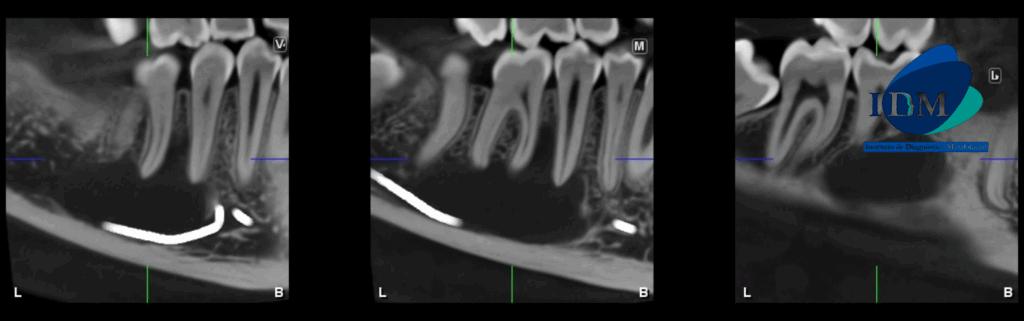

A la evaluación de la tomografía volumétrica (CBCT) en los cortes axiales (Figura 2) y transaxiales (Figura 3), se aprecia imagen isodensa de limites definidos, que se extiende en sentido cefálico caudal desde tercio medio radicular de pieza 46 hasta borde basal mandibular, en sentido mesio distal desde mesial de pieza 45 hasta apical de pieza 47, que ocasiona desplazamiento del conducto dentario inferior hacia caudal y borramiento parcial de la cortical superior de la misma, adelgazamiento de tabla ósea lingual.

CORTES TANGENCIALES